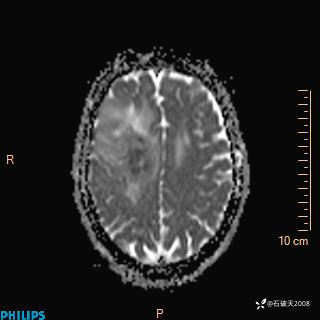

2024.2.21MR

DWI